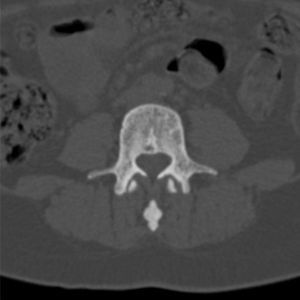

En un control radiográfico rutinario de la columna lumbar (fig. 1), se observan numerosos focos pequeños, bien definidos, homogéneos, circulares, de mayor densidad ósea, en los cuerpos vertebrales, a lo largo de todo el esqueleto axial, por lo que se amplía estudio con radiografía de pelvis AP (fig. 2) y TAC de pelvis y cuerpo vertebral lumbar (figs. 3 y 4), que mostraban lesiones radiodensas redondeadas u ovales en la cabeza y el cuello femorales y en regiones pertrocantéreas, con presencia de pequeñas áreas de densidad aumentada en la pelvis y en los cuerpos vertebrales que indicaban como primer diagnóstico osteopoiquilia. No se observaban componente de partes blandas, ni áreas de rotura de la cortical, ni presencia de reacciones periósticas de características agresivas.